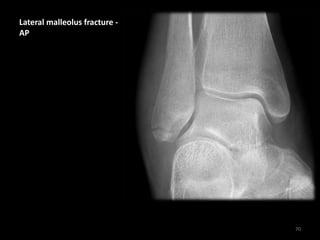

Lateral malleolus fracture -

AP

70

• Soft tissue swelling

laterally (asterisks)

• Transverse fracture of

fibular tip (Weber A)

• The ankle joint remains

aligned normally

• Weber A = Distal

to ankle joint (this case)

• Weber B = At level

of ankle joint

• Weber C = Proximal

to ankle joint